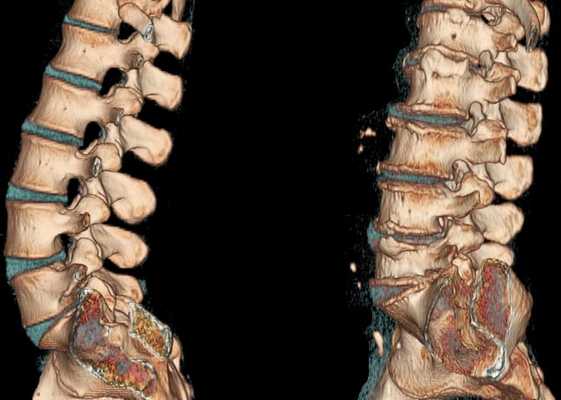

При остеохондрозе пульпозное ядро теряет свои гидрофильные свойства. Это происходит из-за нарушений в его метаболизме или недостаточного поступления необходимых веществ. В результате межпозвонковый диск становится плоским и менее упругим, в его фиброзном кольце при нагрузке появляются радиальные трещины. Уменьшается расстояние между соседними позвонками и они смещаются по отношению друг к другу, при этом происходит смещение и в фасеточных (дугоотростчатых) суставах, соединяющих позвонки.

Разрушение соединительной ткани фиброзного кольца диска, связок и капсул фасеточных суставов вызывает реакцию иммунной системы и развитие асептического воспаления с отечностью фасеточных суставов и окружающих их тканей. Из-за смещения тел позвонков происходит растяжение капсул фасеточных суставов, а измененный межпозвонковый диск уже не так прочно фиксирует тела соседних позвонков. Формируется нестабильность позвоночного сегмента. Из-за нестабильности возможно ущемление корешка спинномозгового нерва с развитием корешкового синдрома. При остеохондрозе шейного отдела позвоночника это часто возникает во время поворотов головой, при остеохондрозе поясничного отдела — во время наклонов туловища. Возможно формирование функционального блока позвоночно-двигательного сегмента. Он обусловлен компенсаторным сокращением позвоночных мышц.

При остеохондрозе происходит разрастание костной ткани с образованием остеофитов — костных выростов на телах и отростках позвонков. Остеофиты также могут вызвать сдавление спинного мозга (компрессионную миелопатию) или стать причиной развития корешкового синдрома.